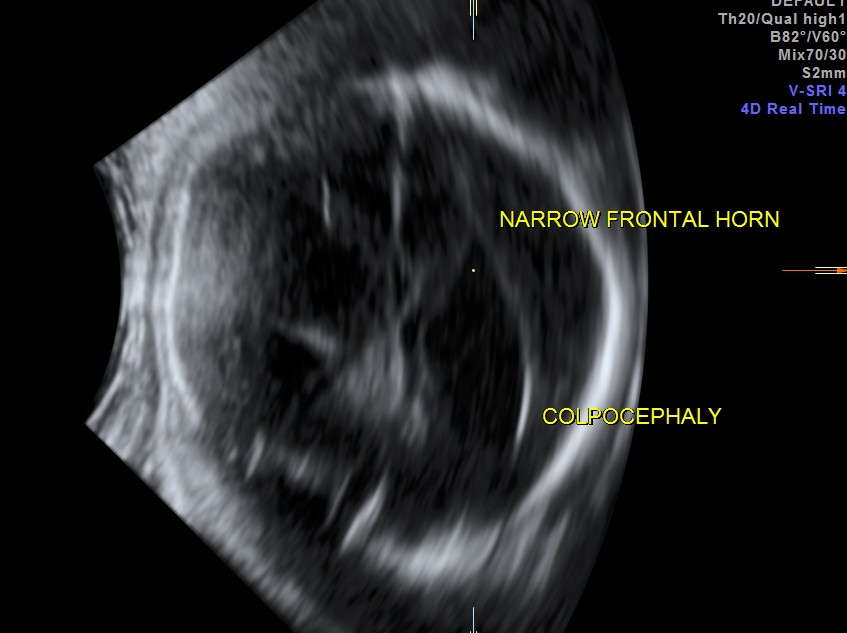

prominent ventriculomegaly of posterior horns of both lateral ventricles – colpocephaly

demonstration of both medial and lateral ventricular walls at a level where the single periventricular line is normally demonstrated

- demonstration of both medial and lateral ventricular walls at a level where the single periventricular line is normally demonstrated, and

- a more parallel course of both ventricular walls than normal.